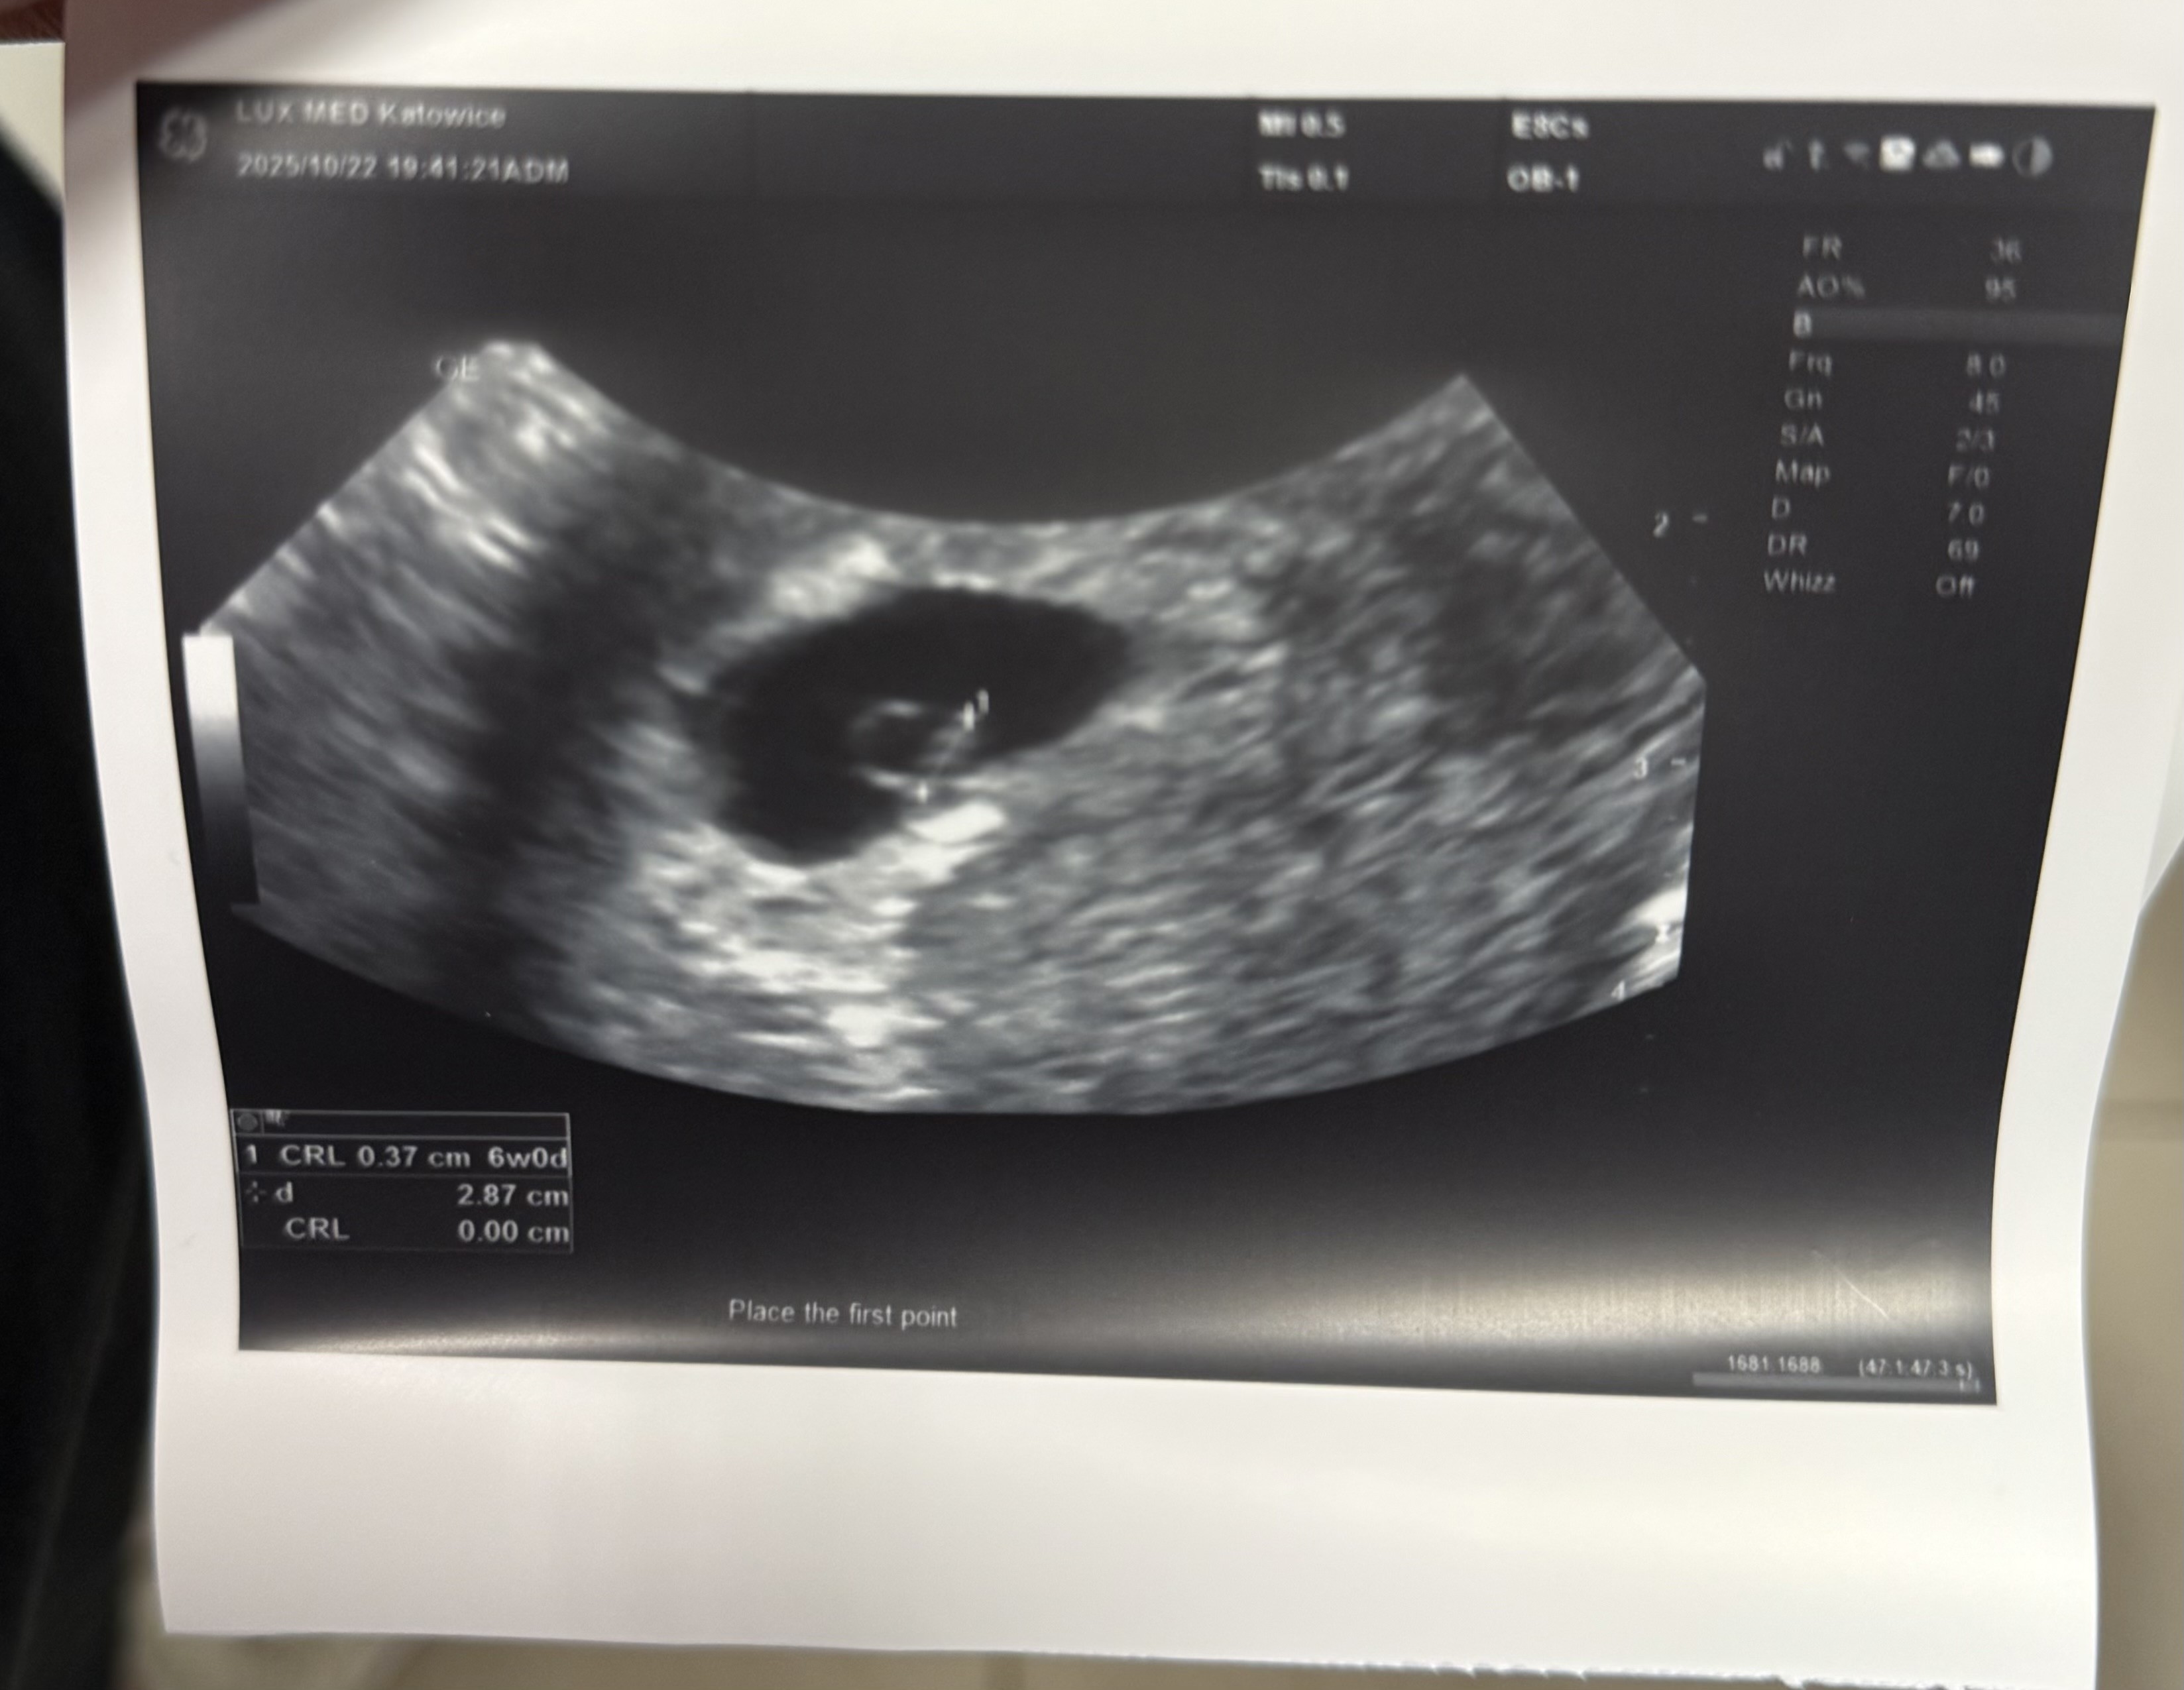

cudowny widok, gratulacje!Hej dziewczyny, ja dziś już po drugiej wizycie mamy 6+0 i zobaczyliśmy na wizycie zarodek 3,7mm i pulsujące serducholekarz założył kartę ciąży i widzimy się za dwa tygodnie, normalnie byłoby za 3 natomiast idzie na urlop i zobaczymy się wcześniej, co dla mnie oczywiście jest lepszym wyjściem, AAAA ale jestem szczęśliwa

Bardzo się cieszę gratulujęHej dziewczyny, ja dziś już po drugiej wizycie mamy 6+0 i zobaczyliśmy na wizycie zarodek 3,7mm i pulsujące serducholekarz założył kartę ciąży i widzimy się za dwa tygodnie, normalnie byłoby za 3 natomiast idzie na urlop i zobaczymy się wcześniej, co dla mnie oczywiście jest lepszym wyjściem, AAAA ale jestem szczęśliwa